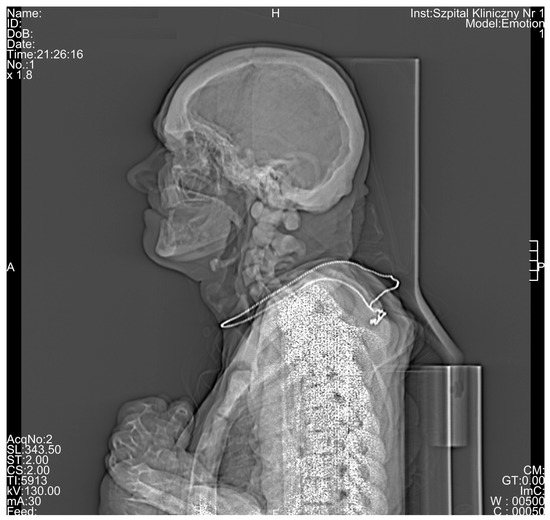

Computed Tomography Diagnostic of Uncommon Case of Osteopetrosis in 80-Year-Old Man—Case Report

3. Results